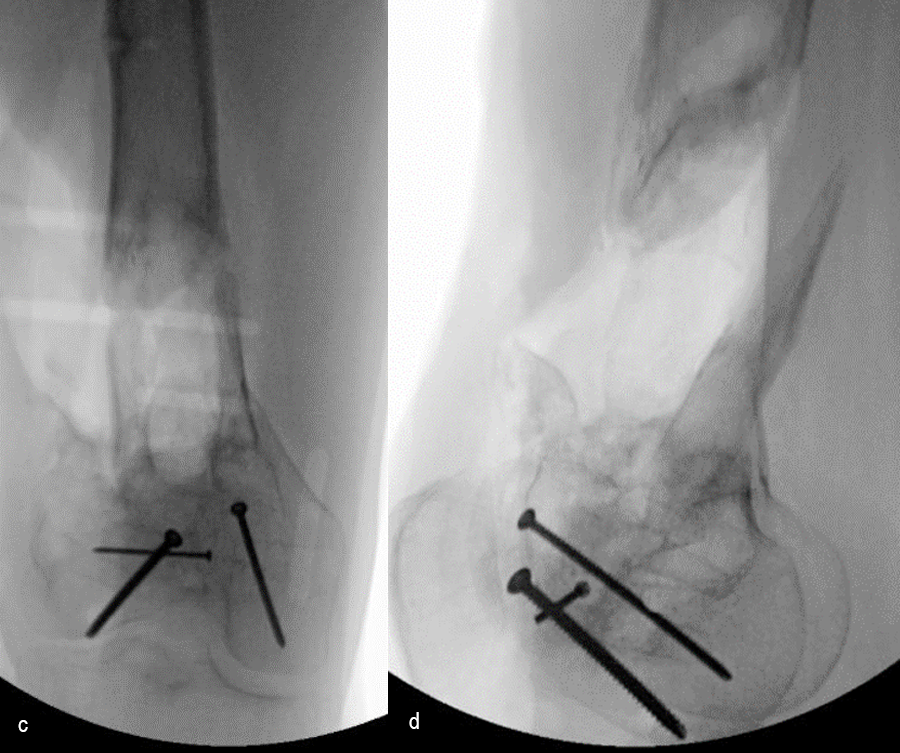

In a first stage, the distal humerus was debrided and devitalized bone was resected, leaving an 8cm defect into which a cement spacer was placed. New plates were inserted to stabilize the fracture (Fig 17 and Fig 18). Cultures taken in the OR were negative.

In October 2022, planning began for the second stage of surgery. A graft cage was planned (Fig 19) to allow the formation of new bone in the 8cm defect.

The second stage of surgery took place in October 2022. The cage was inserted (Figs 20-22) and filled with ~20cc autograft obtained by RIA of the femur, 30cc allograft and 3cc BMAC.